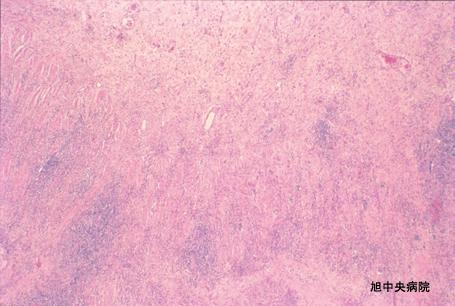

일레우스 증상을 보인 허혈성 소장염의 수술예 (증례제시:치바현 아사히시 아사히중앙병원)

염증성 및 궤양성질환/허혈성 장염(혈전증 포함)

소장/회장

마이크로